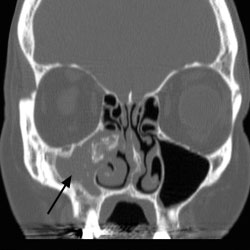

Fungus Ball

A fungus ball occurs when there is an overgrowth of fungal elements in the sinuses, particularly the maxillary and the sphenoid sinuses, where the fungus thrives in the warmth and humidity. Common molds such as…